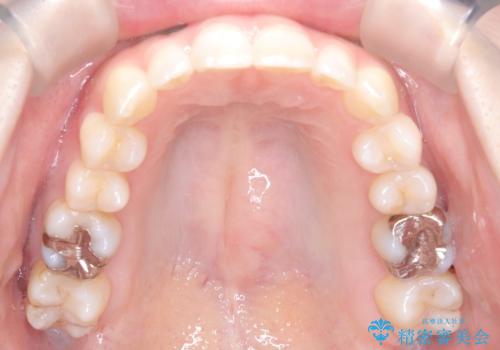

インビザラインで整えた前歯の歯並び

- 患者様は、上下前歯の歯列不正(ガタガタ)を主訴としてご来院されました。治療計画として、透明なマウスピース型矯正装置「インビザライン」を使用し、約2年の期間を見込んで前歯部の歯列を整える方針を立てました。特に下顎前歯に歯肉退縮のリスクがあるため、治療中にIPR(インタープロキシマルリダクション)を行い、歯間を適切に削ることで、過度な圧力を避け、歯肉退縮を防ぎながら配列を進めました。治療は慎重に進め、最終的にきれいで整った前歯の歯並びを目指しました。

インビザラインによる矯正治療は、患者様自身が装着するマウスピース型の装置を使用するため、装着時間の徹底が重要です。特に、下顎前歯の歯肉退縮を避けるため、IPRを施すことで歯間スペースを確保し、歯肉にかかる負担を減らしました。この方法により、歯並びを整えながらも歯肉の健康を保つことができます。治療期間中は定期的にチェックを行い、歯肉の状態や歯の動きを慎重に確認しました。また、治療後はリテーナーを装着して歯並びを維持し、安定させました。